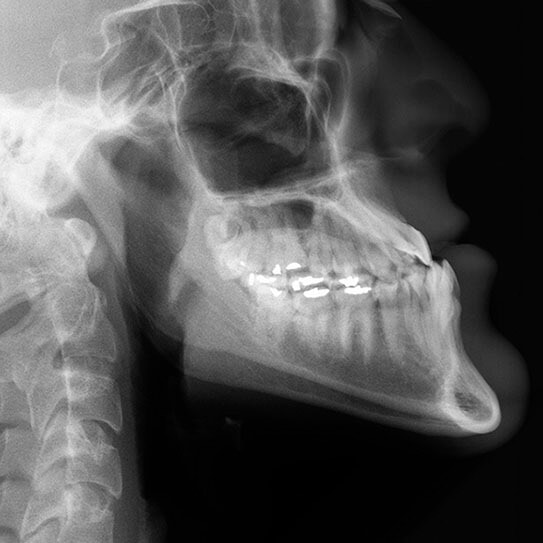

Types of Malocclusions

OUR TEETH ARE MEANT to fit together in a specific way. It’s how we are able to chew effectively and speak clearly. When the upper and lower teeth don’t fit together the way they should, we call that a malocclusion, or bad bite. In addition to impeding those important functions, a malocclusion can also result in jaw problems, put teeth at risk of breaking, and even make digestion less efficient.

When the jaw is closed in a healthy bite, the upper teeth should rest slightly over the lower teeth, and the points of the upper molars should fit into the grooves of the lower molars. Let’s go over five of the most common ways a bite can veer off of what is healthy.

• Excessive overbite: the upper teeth overlap or overjet the lower teeth by too much for a healthy bite.

• Deep bite: such a severe overbite that the upper front teeth completely overlap the lower front teeth, which may even drive into the gums behind the upper teeth, risking injury to the gum tissue.

• Open bite: sometimes the result of a tongue thrust habit or aggressive thumbsucking in the preschool years and beyond, the upper front teeth flare out, leaving a gap between them and their lower counterparts when biting down.

• Crossbite: when the jaw is closed, some upper teeth are on the outside and some lower teeth are on the outside.

• Underbite: when the jaw is closed, the lower teeth jut out in front of the upper teeth.

Orthodontic Treatment: The Solution to Malocclusions

Orthodontic treatment can correct any of these bad bites, and these days, it can do it with less of the bulky headgear we sometimes see in older movies. Jaw surgery is also a less common solution today, though some severe cases still require it. Modern treatment for malocclusions tends to be much more low profile and hassle free, and we love being able to offer these kinds of solutions.